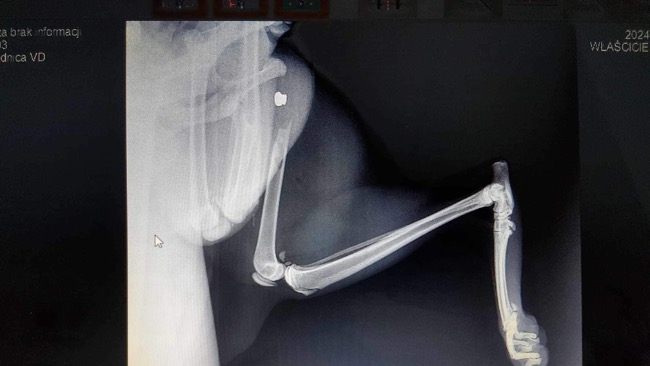

przyszla w nocy 6 maja do domu i juz wtedy miala problem z chodzeniem (kulala). zastanawialismy sie co sie dzieje, zaczekalismy jeden dzien przed pojsciem do weterynarza (w nadzieji ze moze jej przejdzie). 8maja udalam sie z kicia do weterynarza. na miejscu dostalam wiadomosc, ze noga jest zlamana i potrzebne jest rtg. po zrobieniu przeswietlenia wszystko bylo jasne - zlamanie przez postrzelenie wiatrowka. kosc zlamana w udzie. potrzebna jest operacja, ale koszt jest bardzo wysoki, mianowicie (z antybiotykami) moze wyjsc nawet kolo 4 tysiecy zlotych. apeluje o pomoc w sfinansowaniu tej operacji, bedziemy bardzo wdzieczni. shisha, choc jest tylko kotem, wiele dla nas znaczy, traktujemy ja jak czlonka rodziny.